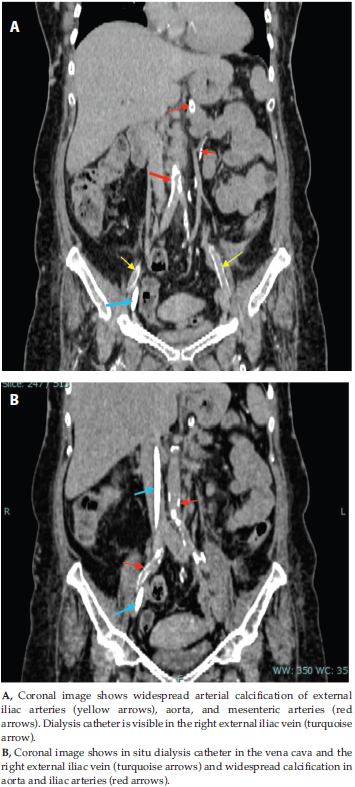

A 28-year-old son (body weight 62 kg, body mass index [measured in kilograms body weight per meter squared] 25) was the donor in the first attempt, and he agreed to donate for the second attempt at transplant to his 55-year-old mother (weight 68 kg, body mass index 31); the mother had end-stage renal disease secondary to 20 years of diabetes and hypertension. This recipient had been on regular hemodialysis for the previous 24 months; the cytotoxic crossmatch was negative with a 5-antigen human leukocyte antigen mismatch. Both donor kidneys were equal in size and had single renal arteries, and the left kidney was selected, despite clear evidence that it had been dissected previously, because the renal vein of the donor’s right kidney was too short. The recipient’s right iliac vein was not usable because of the long-term presence of a long dialysis catheter that occupied the right iliac vein and vena cava (Figure 1).

Figure 1.Computed Tomography Coronal Images of Widespread Arterial Calcification